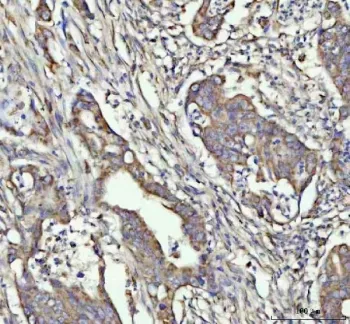

- Applications: WB, IHC-P, ELISA